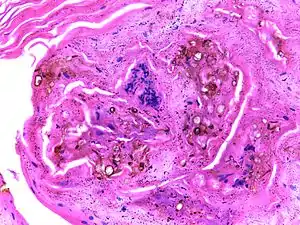

| Micrograph of chromoblastomycosis showing sclerotic bodies | |

The most informative test is to scrape the lesion and add potassium hydroxide (KOH), then examine under a microscope. (KOH scrapings are commonly used to examine fungal infections.) The pathognomonic finding is observing medlar bodies (also called muriform bodies or sclerotic cells). Scrapings from the lesion can also be cultured to identify the organism involved. Blood tests and imaging studies are not commonly used.On histology, chromoblastomycosis manifests as pigmented yeasts resembling "copper pennies". Special stains, such as periodic acid schiff and Gömöri methenamine silver, can be used to demonstrate the fungal organisms if needed.